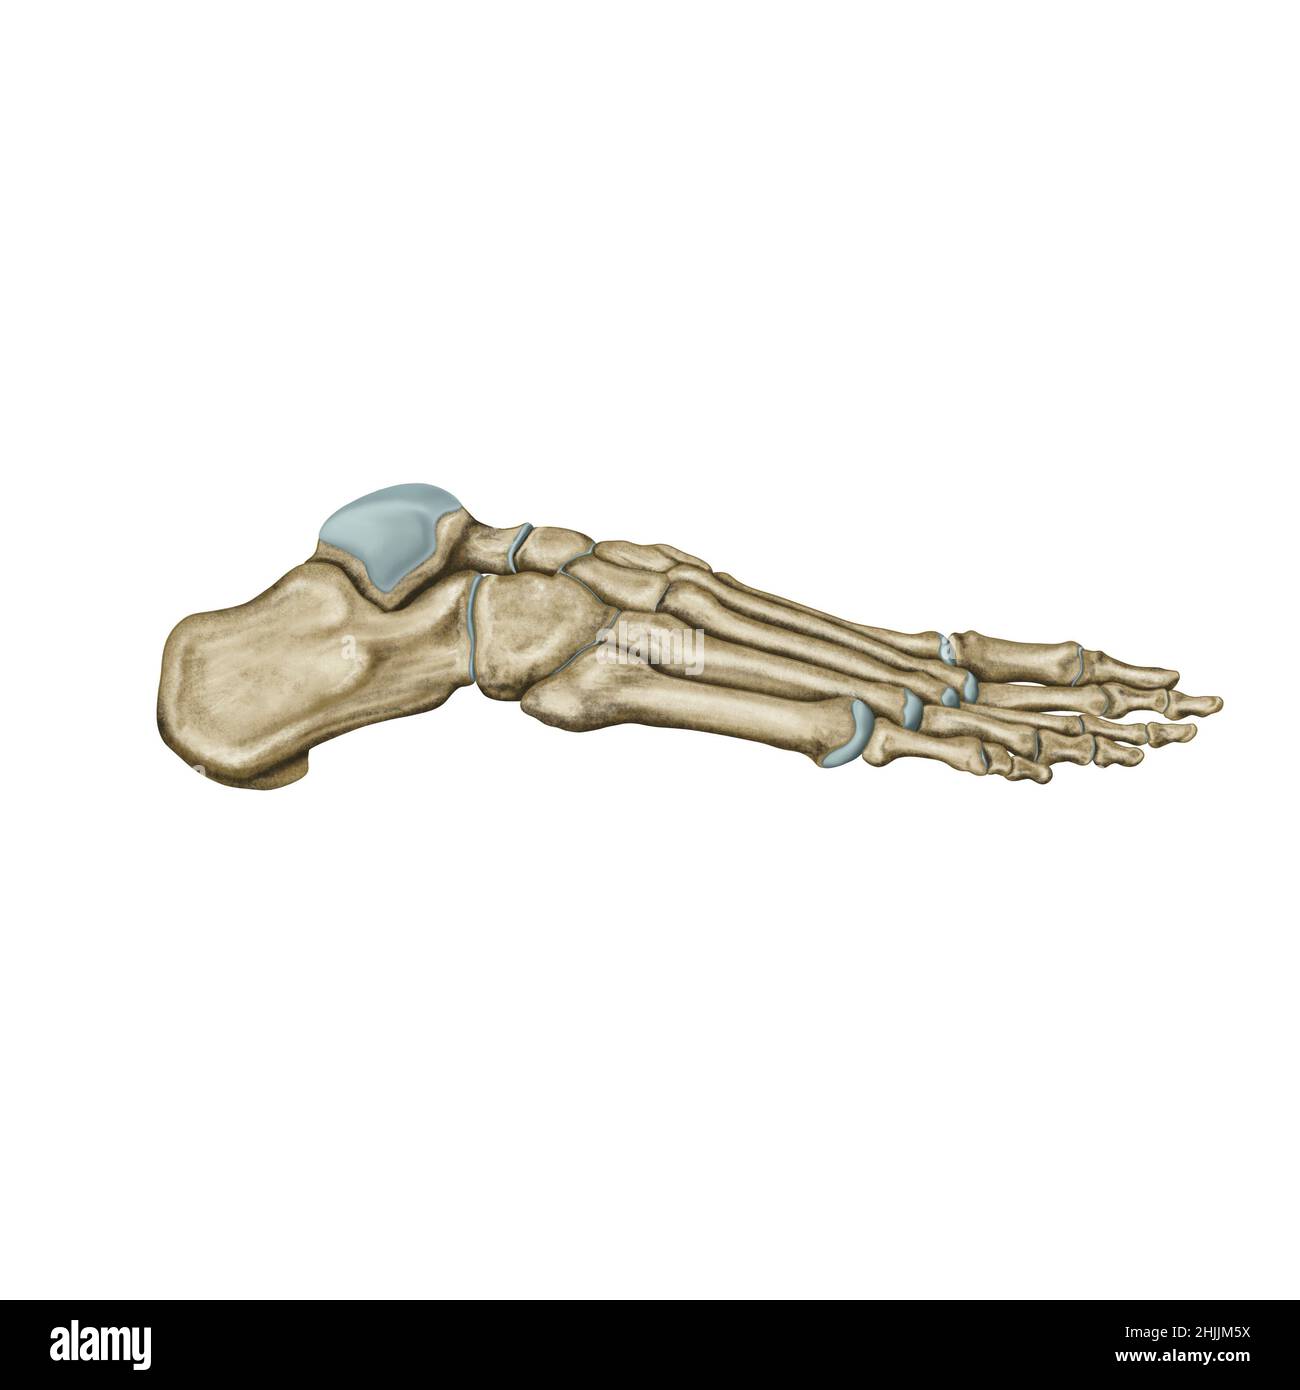

RF2RYN928–Structure du squelette humain aquarelle. OS du pied. Anatomie et médecine. Illustration orthopédique

RMK228DY–Partie terminale du membre inférieur, reposant sur le sol au cours de posture droite ; le squelette du pied a 26 os.

RMK227XM–Partie terminale du membre inférieur, reposant sur le sol au cours de posture droite ; le squelette du pied a 26 os.